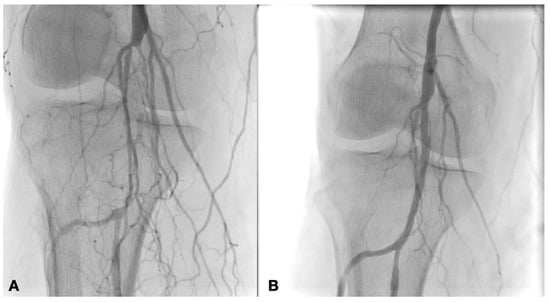

2.2. Technique